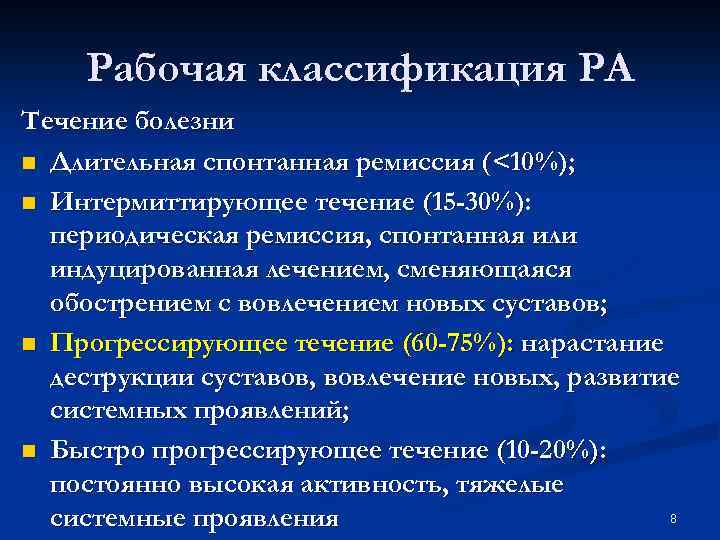

Рабочая классификация РА Течение болезни n Длительная спонтанная ремиссия (<10%); n Интермиттирующее течение (15 -30%): периодическая ремиссия, спонтанная или индуцированная лечением, сменяющаяся обострением с вовлечением новых суставов; n Прогрессирующее течение (60 -75%): нарастание деструкции суставов, вовлечение новых, развитие системных проявлений; n Быстро прогрессирующее течение (10 -20%): постоянно высокая активность, тяжелые 8 системные проявления

Рабочая классификация РА Течение болезни n Длительная спонтанная ремиссия (<10%); n Интермиттирующее течение (15 -30%): периодическая ремиссия, спонтанная или индуцированная лечением, сменяющаяся обострением с вовлечением новых суставов; n Прогрессирующее течение (60 -75%): нарастание деструкции суставов, вовлечение новых, развитие системных проявлений; n Быстро прогрессирующее течение (10 -20%): постоянно высокая активность, тяжелые 8 системные проявления